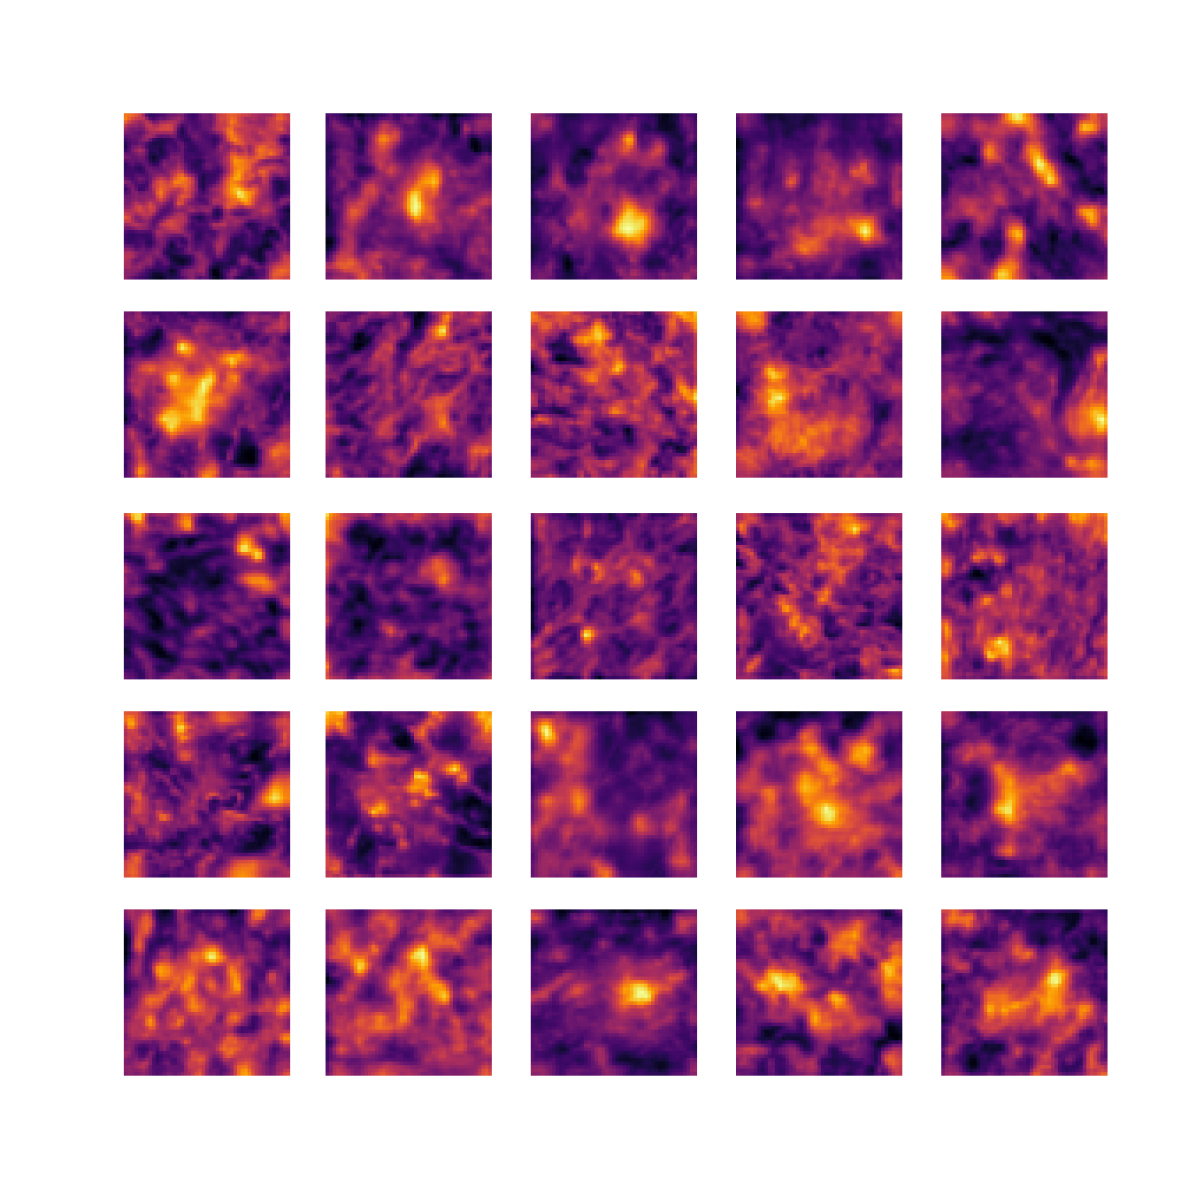

We also analyse the activation maps for each model using GradCAM as described in section S3. This offers more insight into the areas of the image which are contributing most heavily to the models’ representations. In Figure 4(b) we present some representative examples, however, a larger selection which was chosen at random is presented in Figures S10 to S25. The larger selection makes it easier to see the emergent patterns, including that privileged Siamese models tend to mainly identify features which are strongly present in both inputs, while unprivileged Siamese models tend to learn more diffuse features that are not specific to one cell phenotype or image region. TriDeNT ♆ incorporates both sets of features, learning both features specific to the privileged data and more the general features associated with unprivileged Siamese networks.

We can see in Figure 4(b) panel A that for ERG, the privileged Siamese model focuses almost exclusively on any nuclei which could be endothelial cells. As there are very few endothelial cells in the dataset, it could be an effective strategy to identify anything that could potentially be an endothelial cell to minimise the difference between the representations of the H&E model and the IF mask model. In the corresponding unprivileged Siamese image, we see that the model identifies some of these nuclei, albeit less strongly, but also focuses heavily on the other tissue and even the background, while strongly fixating on two spots of debris in the center of the image. This model has less ‘incentive’ to learn the weak features related to endothelial cells as these occur rarely and are not easy to detect, while more generic strong features such as the presence of connective tissue and the prevalence of background are more common and predictable from augmented images. We see that TriDeNT ♆ combines these two feature sets, strongly identifying nuclei while also identifying the connective tissue.

In panel C we see a similar pattern, with the privileged Siamese model fixating solely on the nuclei, while the TriDeNT ♆ model takes a more balanced approach. The unprivileged Siamese model appears to focus on a single cluster of nuclei while neglecting others, and similarly identifies an area of fibroblasts with its distinctive pattern but does not others.

In contrast to panels A and C which represent models with poor privileged Siamese results, panels B and D represent models whose privileged Siamese results were comparable to both TriDeNT ♆ and even the supervised baseline. It is therefore interesting to note that there are far more similarities between the privileged Siamese and TriDeNT ♆ models in both cases. Particularly in panel B, TriDeNT ♆ and the privileged Siamese model return virtually identical heatmaps, with both strongly identifying epithelial nuclei and neglecting the same areas of connective tissue. The unprivileged model in this case appears to focus solely on the centre of the image, giving a significantly different heatmap to the other panels.

Panel D again shows the previous pattern, with the privileged Siamese model identifying the features strongly present in the privileged data – fibroblasts – while neglecting the nuclei present. TriDeNT ♆ also strongly identifies the connective tissue, but, unlike the privileged Siamese model, does not completely neglect the nuclei. The unprivileged Siamese model primarily identifies background, and does not appear to identify the nuclei in this example.